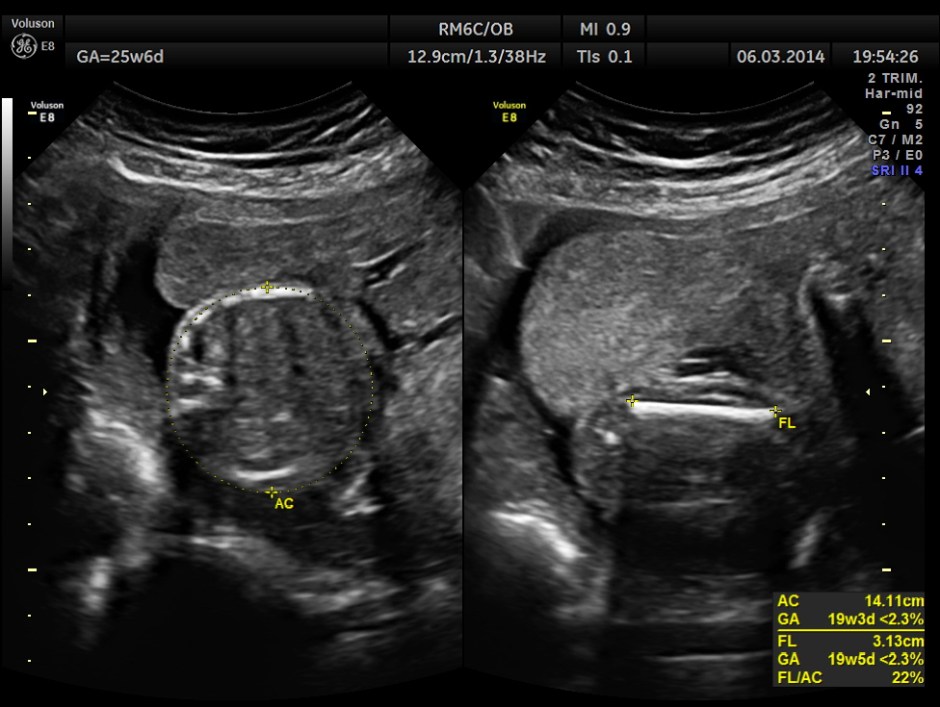

The GA was around 25 weeks , but the AUA was around 19 to 20 weeks. All parameters – BPD, HC, AC, FL are < 2.3 %tile and all other long bones are < 5.0 %tile.

Oligohydramnios seen.